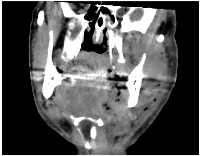

Figure 2: Contrast-enhanced CT scan demonstrating hallmark features of cervicofacial necrotizing fasciitis.

Coronal

contrast-enhanced computed tomography (CT) image of a patient with cervicofacial necrotizing fasciitis, illustrating characteristic

radiologic features including diffuse fascial thickening, gas formation in the subcutaneous and deep cervical spaces, and fluid collections

extending along fascial planes.